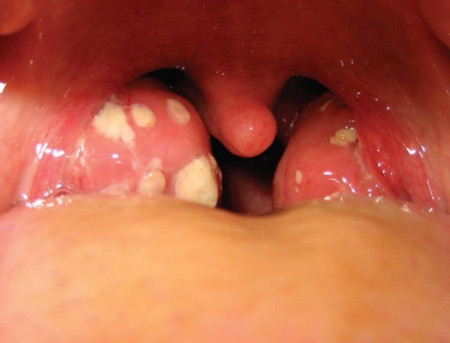

Белые пятна на гландах свидетельствуют о поражении этого органа каким-либо заболеванием. Чтобы не довести ситуацию до хирургического вмешательства, необходимо срочно выяснить причину налета и начать правильное лечение.

Белые пятна — это образовавшиеся на миндалинах комочки небольшого размера, имеющие белый или желтый цвет. Их можно разглядеть невооруженным глазом перед зеркалом, широко раскрыв рот.

Они имеют густую консистенцию и состоят из гноя и белых кровяных телец — погибших микроорганизмов.

Гланды имеют пористую поверхность. Углубления, имеющиеся на них, называются лакунами. В лакунах задерживаются микробы и вирусы. При нормальной работе иммунной системы вредоносные бактерии уничтожаются организмом.

Если иммунитет человека снижен, то появляются белые пятна на миндалинах, свидетельствующие о нарушениях в организме человека.